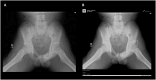

Missed fractures are a costly healthcare issue, not only negatively impacting patient lives, leading to potential long-term disability and time off work, but also responsible for high medicolegal disbursements that could otherwise be used to improve other healthcare services VSports手机版. When fractures are overlooked in children, they are particularly concerning as opportunities for safeguarding may be missed. Assistance from artificial intelligence (AI) in interpreting medical images may offer a possible solution for improving patient care, and several commercial AI tools are now available for radiology workflow implementation. However, information regarding their development, evidence for performance and validation as well as the intended target population is not always clear, but vital when evaluating a potential AI solution for implementation. In this article, we review the range of available products utilizing AI for fracture detection (in both adults and children) and summarize the evidence, or lack thereof, behind their performance. This will allow others to make better informed decisions when deciding which product to procure for their specific clinical requirements. .